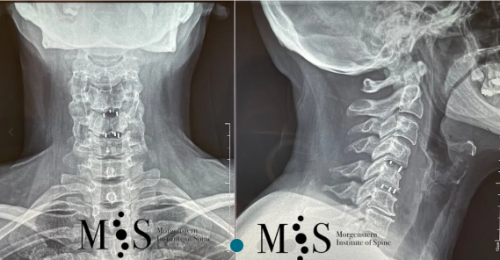

Ejemplo Caso Clínico

Esta paciente de 49 años con una hernia cervical migrada cranealmente en C4/C5 y una inestabilidad en C5/C6 se le realizó una fusión cervical en dos niveles poniendo dos cajas cervicales a través de una incisión en la piel de sólo 2 cm. La recuperación post-operatoria de la paciente fue excelente y muy rápida, pudiéndose dar el alta hospitalaria en menos de 24 horas después de la cirugía.